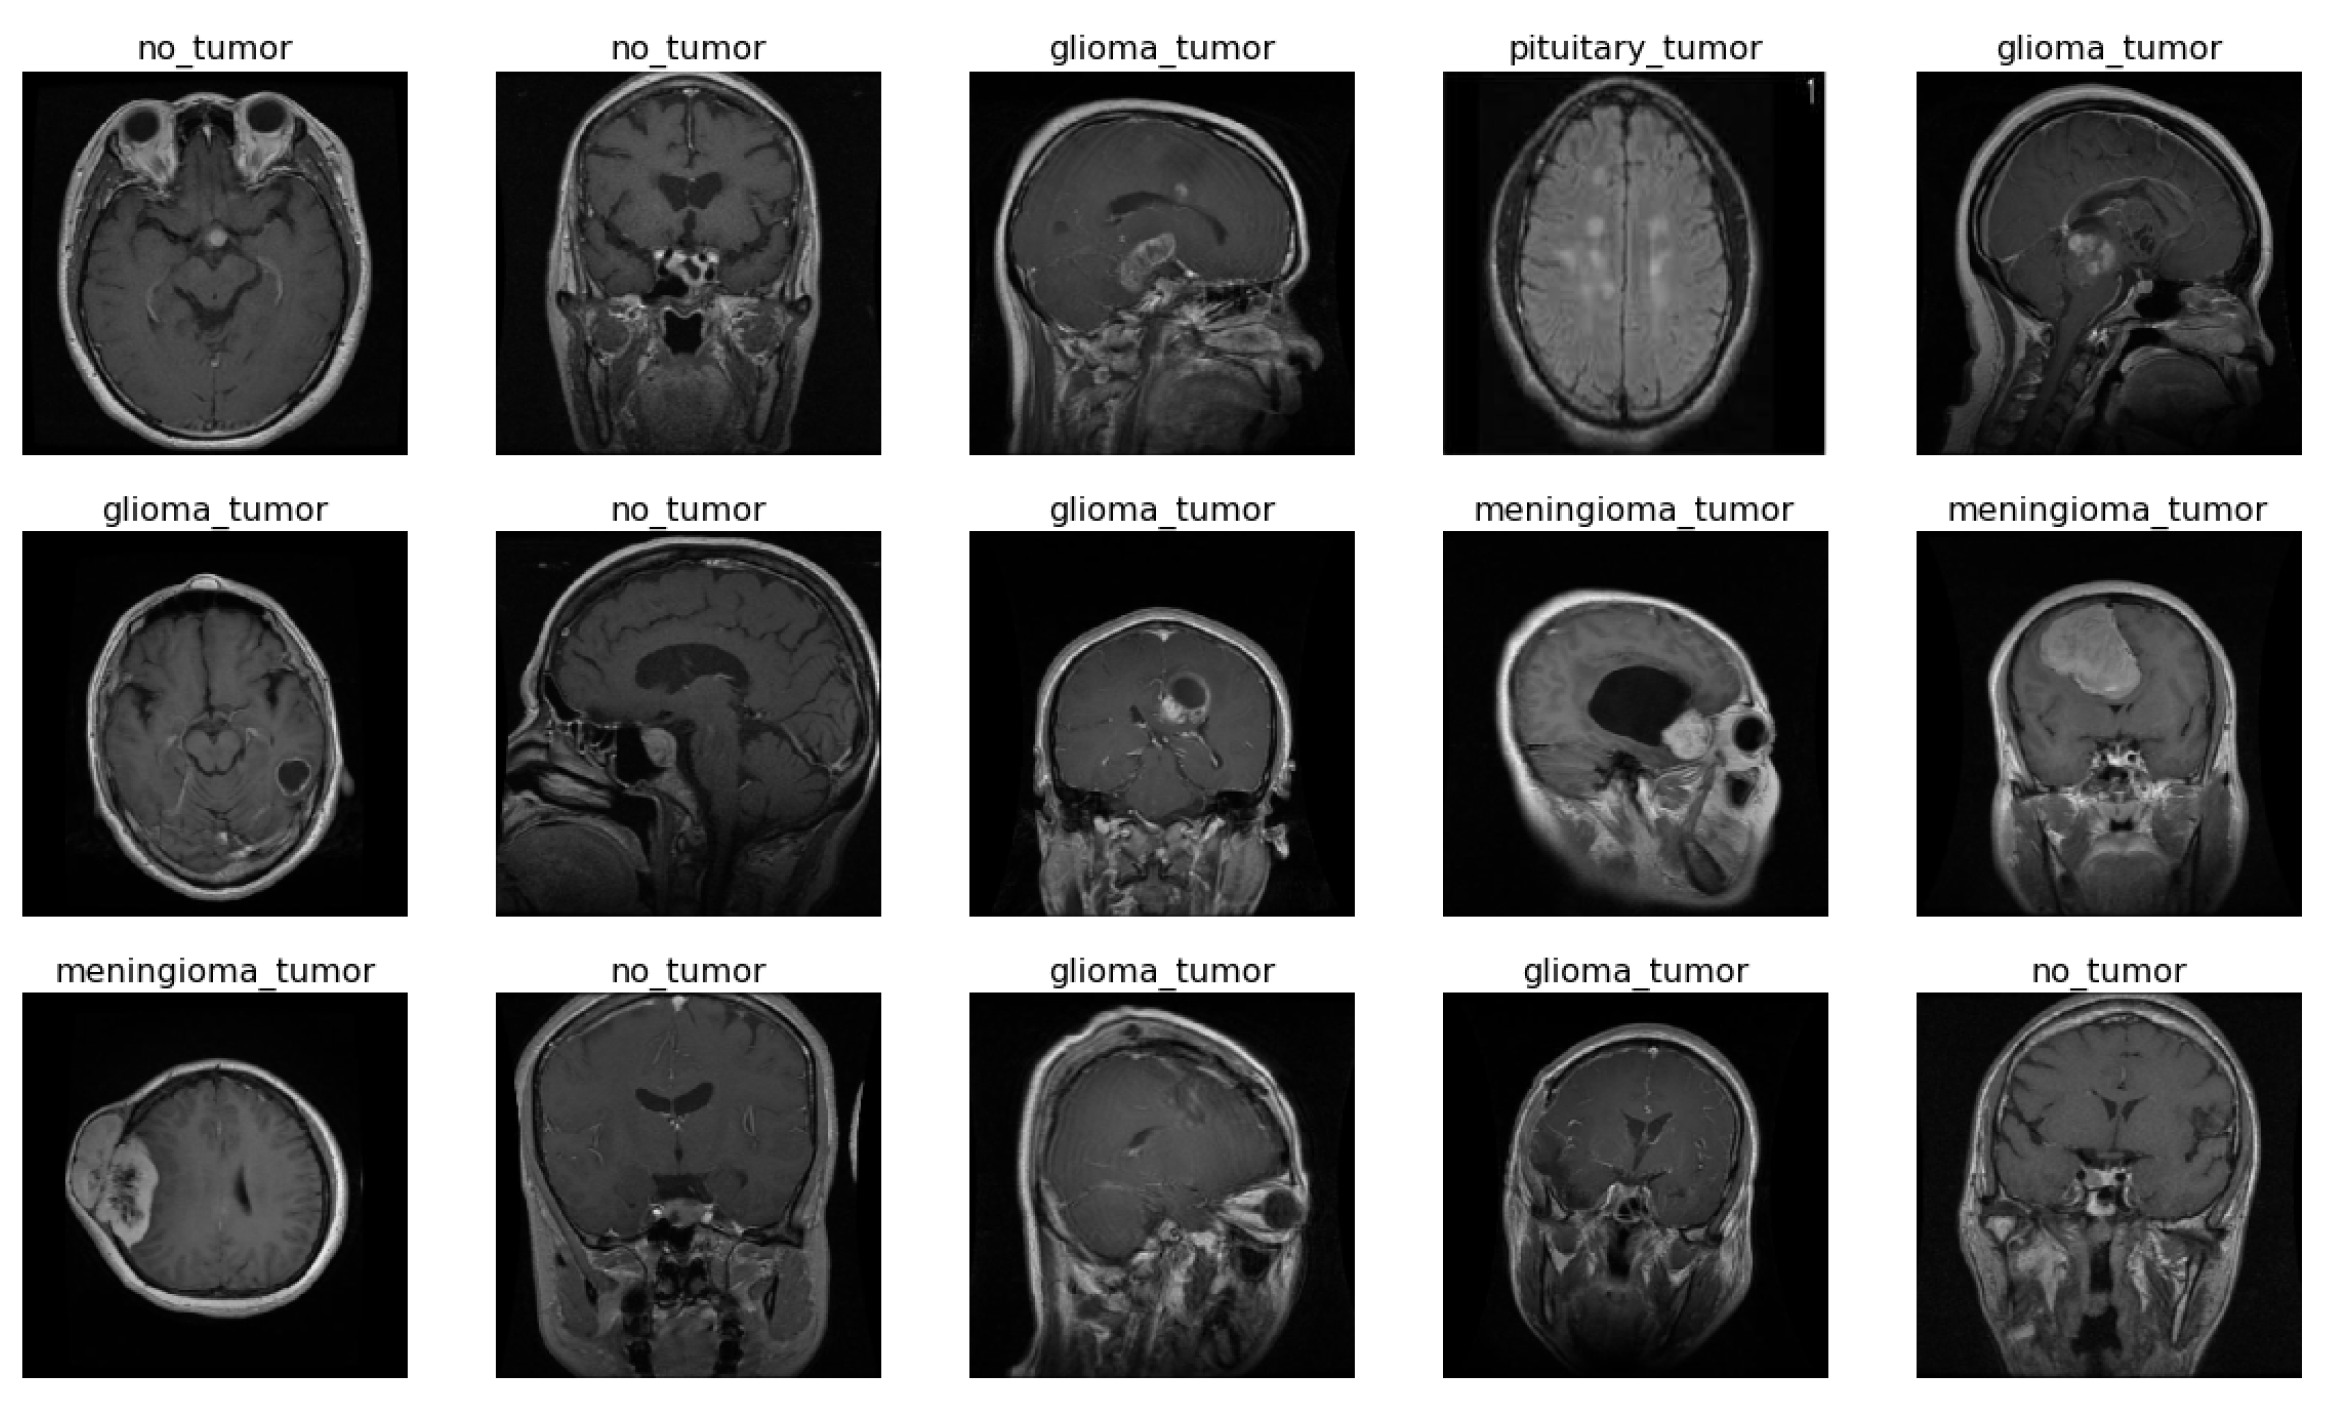

2.1. Dataset

| Class Name | Number of Images | Training | Testing |

| Glioma | 1321 | 1100 | 221 |

| Meningioma | 1339 | 1144 | 195 |

| No tumor | 1595 | 1241 | 216 |

| Pituitary | 1457 | 1370 | 225 |

| Total | 5712 | 4855 | 857 |